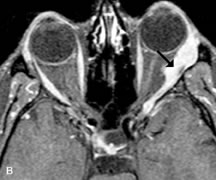

Cavernous hemangiomas appear as well-circumscribed, smooth, usually intraconal masses that are isointense to muscle on T1-weighted images and hyperintense on T2-weighted images (Fig. 12). Patchy early enhancement is typically followed by diffuse, more homogeneous enhancement.39 The internal architecture of the mass, including septation and internal vasculature, may often be appreciated with high-quality orbital imaging.40

Fig. 12. A. T1- and (B) T2-weighted MR scans demonstrate a well-circumscribed intraconal mass causing severe optic nerve displacement. These lesions are usually intermediate in signal intensity on T1-weighted scans and very hyperintense on T2-weighted Images. C and D. Postcontrast fat-suppressed T1-weighted scans demonstrate characteristic patchy intense enhancement that becomes more complete from the initial postcontrast scan (C) to a more delayed scan (D).